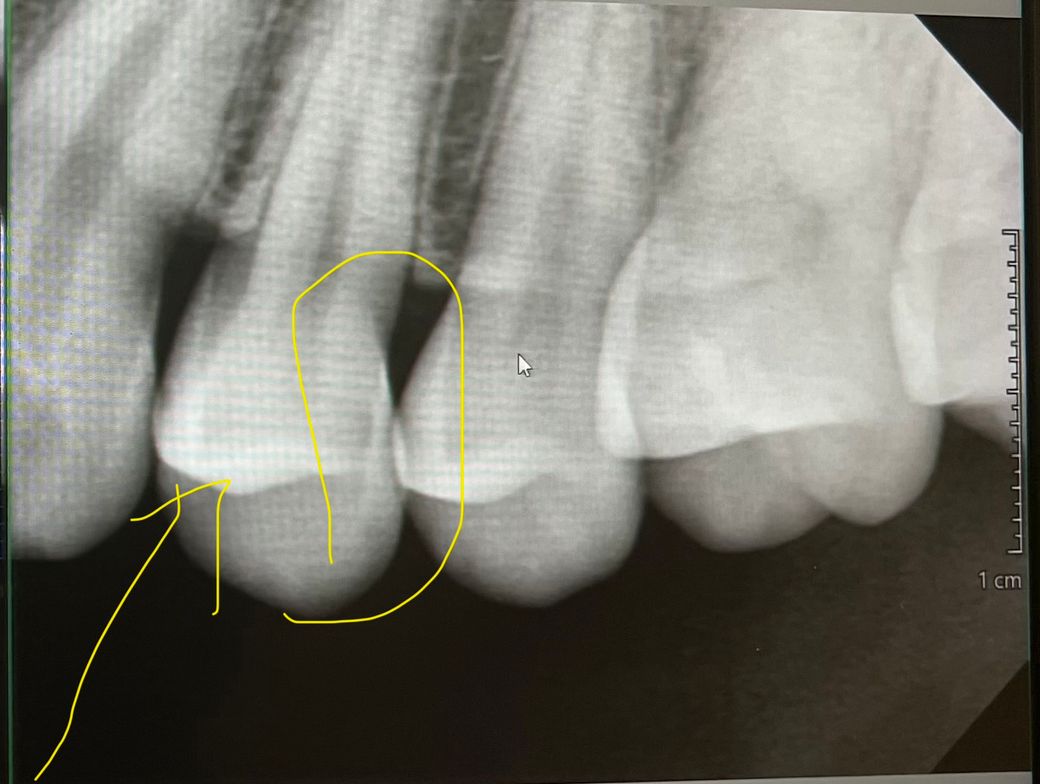

• 1번 째 사진

사진으로는 치아인접면에 색이 변한 부분이 보입니다. 하지만 X레이 사진으로는 충치가 커 보이진 않습니다. 따라서 치실 등으로 해당 부위를 관리해 보는 것이 좋을 것으로 생각되며 주기적으로 치과에서 검진을 받아 충치가 커지고 있지 않은지 확인하는 것이 좋을 것으로 생각됩니다.

1. 육안으로 봤을 때 충치가 보이는 상태 맞고, 안쪽으로 꽤 깊을 수도 있습니다. 방사선 사진에선 보이지 않는데요

2. 아마도, 방사선 사진과 육안 사진이 다른 치아 위치로 보입니다. 확인 해보세요

3. 방사선 사진은 왼쪽 위 작은 어금니 찍은거고, 육안 사진은 오른쪽 위 작은 어금니입니다.